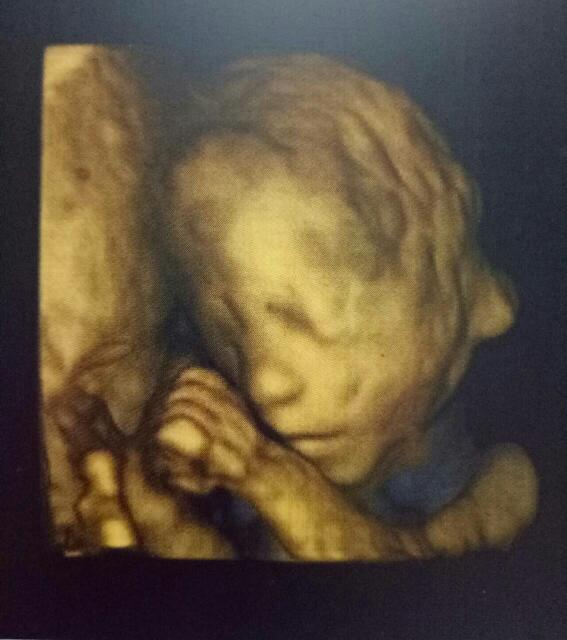

今天去医院做了系统B超,宝宝棒棒哒!顺利通过妈妈还看到了你在吃手手哟!小家伙,妈妈爱你

今天去医院做认坊了系统B超,宝宝棒棒哒!顺利通过😘妈筛险妈还看蔑安径到了你在吃手手哟!小家伙,妈妈爱你